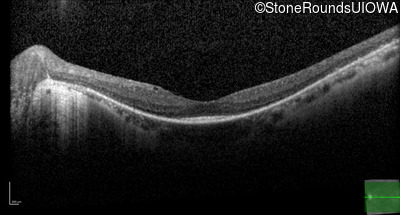

Optical Coherence Tomography - Left - 20/25

Exemplar / OCT Stack